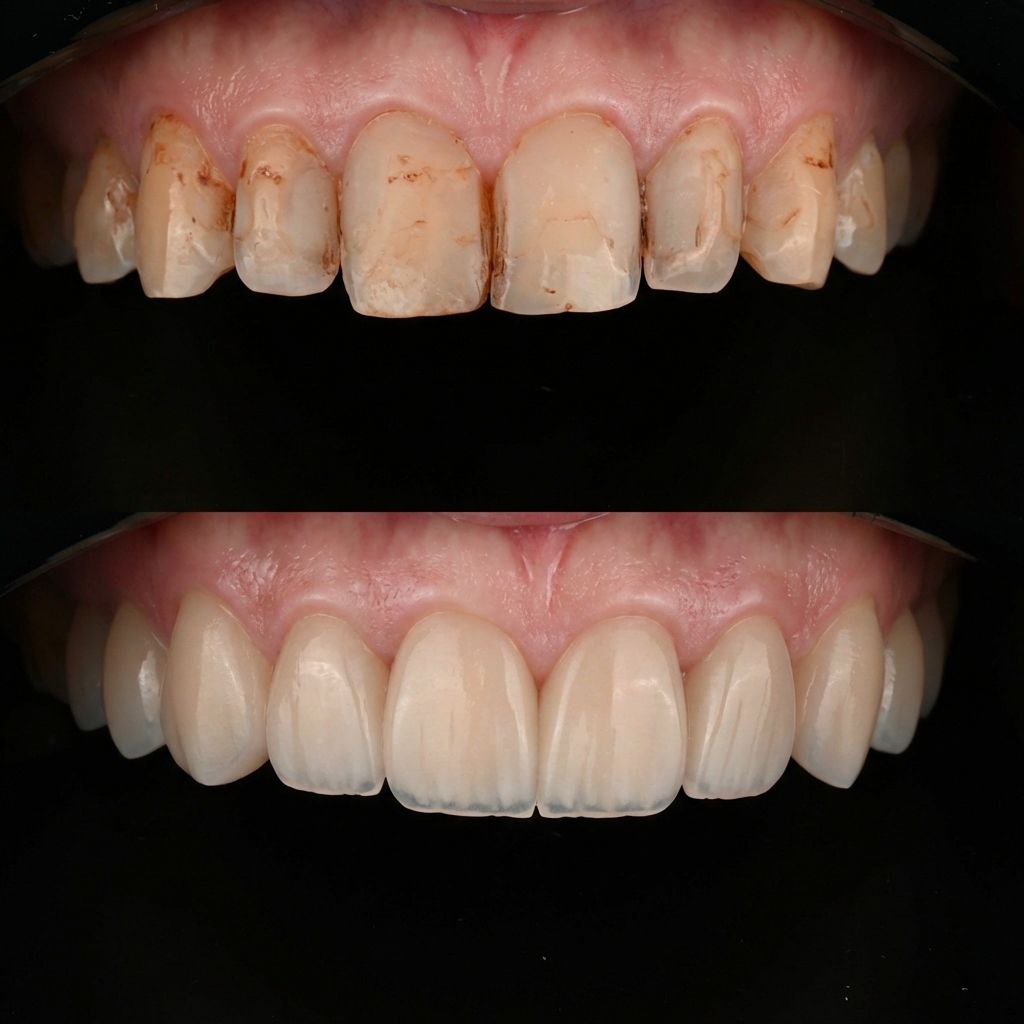

Pulizia e sbiancamento

Servizi di igiene orale per mantenere denti sani e un sorriso brillante nel tempo.